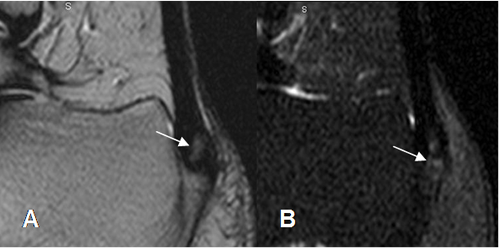

Fig 68. Tendinitis aguda.

A: RM sagital en T2 y B: RM sagital en STIR. Area hiperintensa sobre la inserción del tendón de aquiles, por inflamación aguda.